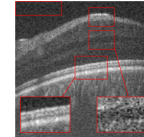

The proposed algorithm has been also tested for the super-resolution of the two other datasets. For dataset2, the middle slices of several 3D image have been selected for test and averaged with 2 previous and 2 next slices. The weights ’s set equal to for each B-scan. For the proposed approach, the patch sizes were set equal to 5 and 7 or (5 and 10) with window size equal to [2,2]. For MDT the window size was set to [2,2]. The results for the super-resolution of artificially missed B-scans of dataset2 with missing ratio have been illustrated in Fig. 6. Since this dataset does not contain reference images, PSNR and SSIM could not be reported. Hence, only visual comparison and the resulting CNR’s, with the following definition, have been reported for each algorithm:

| (14) |

where and are the mean and standard deviation of the foreground respectively and and are the mean and standard deviation of the background region, respectively. Averaged CNR’s for 5 Regions Of Interest (ROI) in each image (relative to an ROI selected in the background region of the image) have been computed. Note that ROI’s have been shown with red boxes in each image of Fig. 6. As the results show, the proposed algorithm results in a better output and higher CNR comparing to the other algorithms.